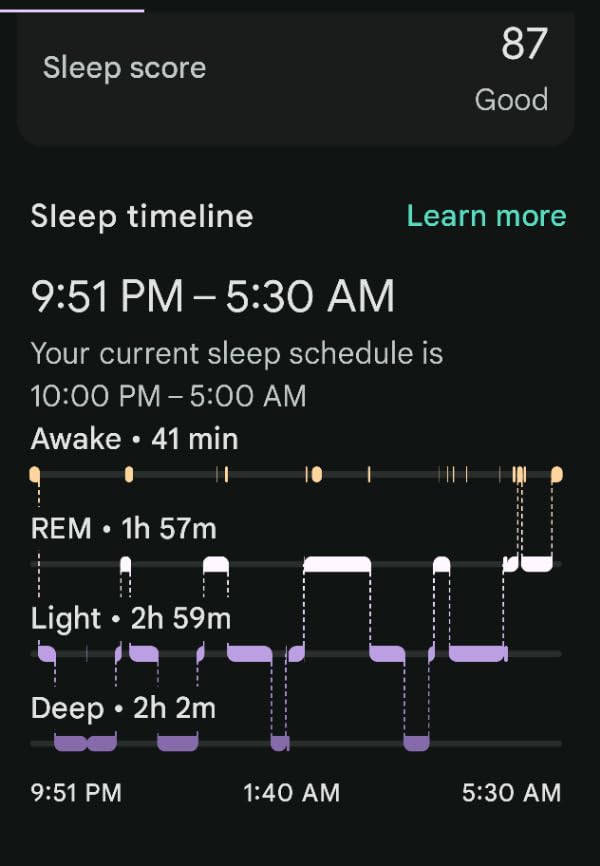

The Calma Clip v2 takes a completely different approach to snoring. Instead of addressing the airway directly, it tackles the root cause for many snorers: sleeping position. This simple device clips onto the back of your shirt and makes back sleeping uncomfortable, naturally training you to stay on your side throughout the night.

As someone who tends to roll onto my back during sleep, I was skeptical that such a simple device could work. But the physics are straightforward. The clip has a plastic exterior with a foam interior that rests against your back. When you roll onto your back, the pressure reminds you to shift back to your side. It's essentially the modern, comfortable version of the old tennis ball trick.

During my two-week trial, I was surprised by how quickly my body adapted. The first few nights, I woke up a couple times when rolling onto my back, but by week two, I was naturally staying on my side without conscious effort. My Fitbit sleep data showed improved sleep quality scores, and my partner confirmed the snoring had virtually disappeared.